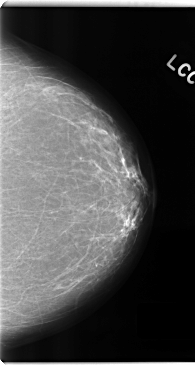

C_0192_1.LEFT_CC

LEFT_CC LINES 4744 PIXELS_PER_LINE 2528 BITS_PER_PIXEL 12 RESOLUTION 50 NON_OVERLAY

LEFT_MLO LINES 4712 PIXELS_PER_LINE 2552 BITS_PER_PIXEL 12 RESOLUTION 50 NON_OVERLAY